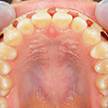

9. 矯正中上顎

可徹式の歯列拡大装置により、術前より若干ですが左右臼歯部の拡大と前歯部顎堤の前方移動を認めます。さらに多少のジスキングにより創出されたスペースを詰めていきます。